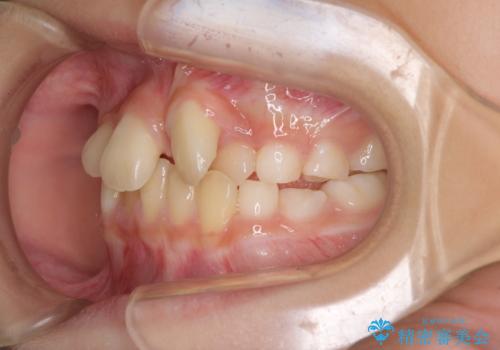

- 前歯の叢生を気にして来院された、小学校3年生女児の患者様です。

身長がやや低く、乳歯から永久歯への交換が少し遅い印象があったので、ワイヤー装置による1期矯正治療ではなく、乳歯も積極的に動かすことのできるインビザライン・ファーストにて治療を行うこととしました。

上顎前歯に過剰歯があったため、まずはその歯を抜歯し、傷が治癒したタイミングでインビザラインを発注することとしました。